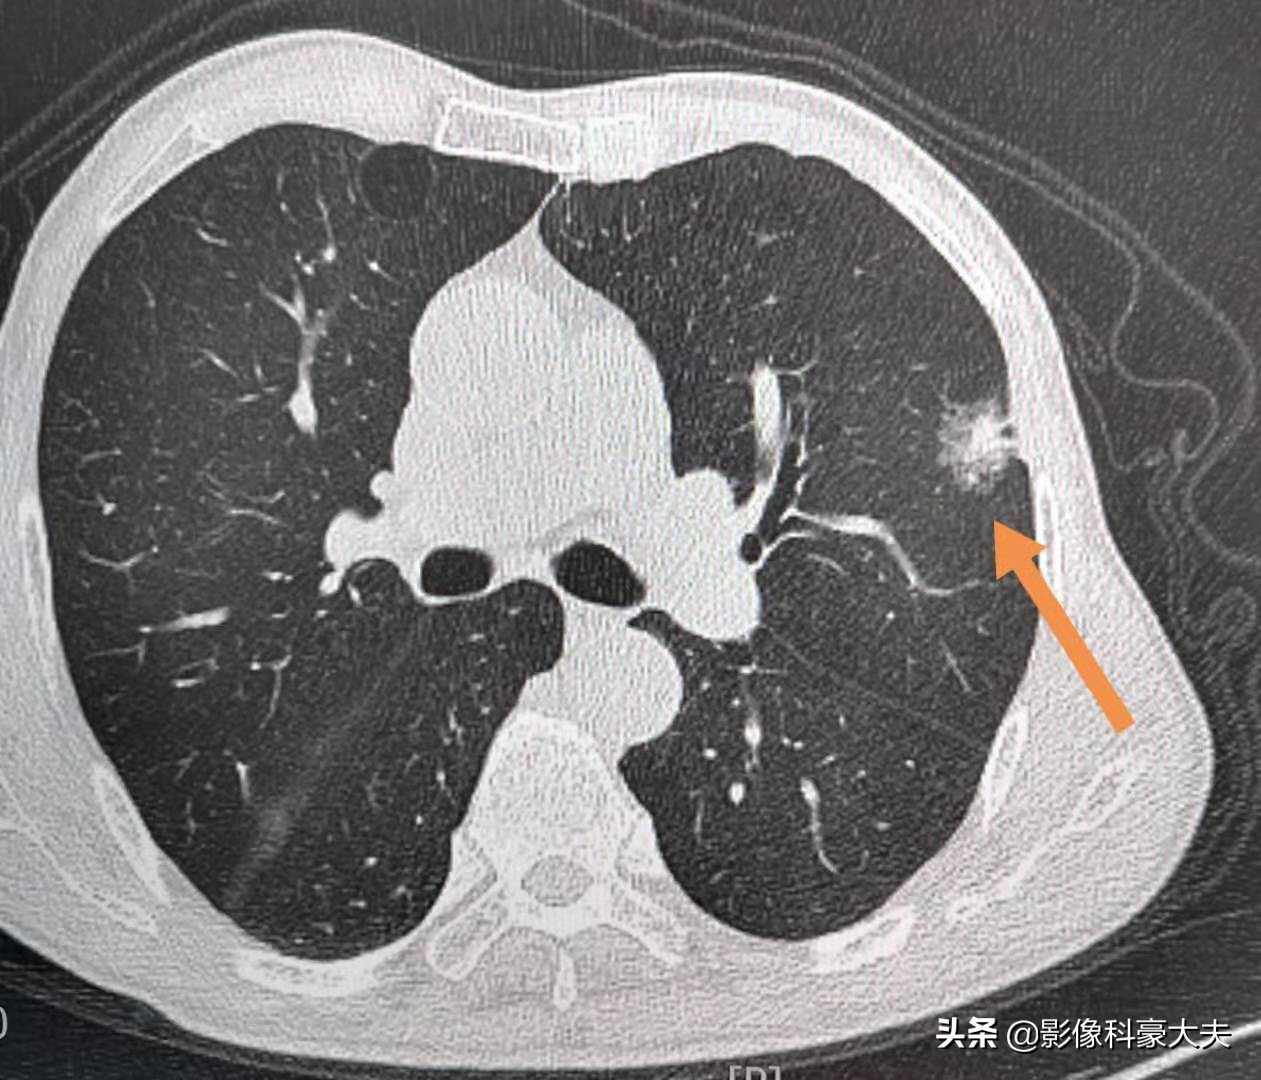

这是另一位老人,状况不好,因为左侧肩背部疼痛几个月,一开始吃点止痛药还有效,后来越来越重,影响到晚上睡眠,结果查了CT发现晚期肺癌。